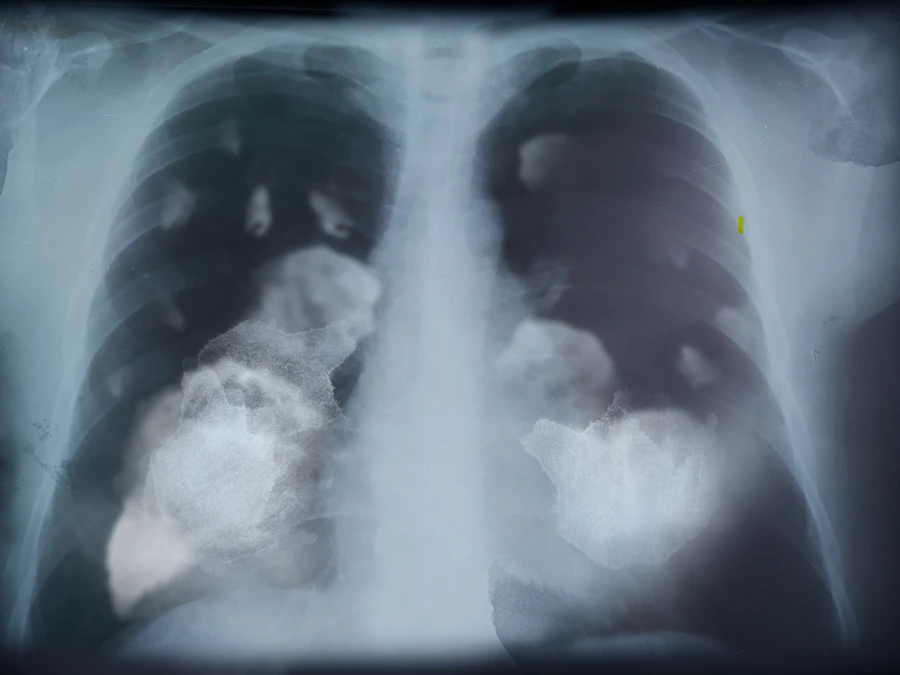

Oft sind es radiologische Untersuchungen, die den ersten Hinweis auf Lungenkrebs geben. Ein auffälliger Befund im Röntgenbild oder in der Computertomografie (CT) führt zu weiteren Abklärungen. Die CT ist besonders genau und kann selbst kleine Veränderungen sichtbar machen. In unklaren Fällen folgen weitere Verfahren wie eine Bronchoskopie (Lungenspiegelung) oder eine Gewebeprobe. Auch zur Planung der Behandlung liefert die Radiologie wichtige Informationen – etwa zur Größe und Ausbreitung des Tumors.

Die Niedrigdosis-Computertomografie (Low-Dose-CT oder LDCT) ist ein spezielles Röntgenverfahren mit besonders geringer Strahlenbelastung. Sie ermöglicht sehr genaue Aufnahmen der Lunge – deutlich präziser als ein normales Röntgenbild – und kann selbst kleine, noch symptomfreie Tumoren sichtbar machen. Genau hier liegt ihr Wert für die Früherkennung.